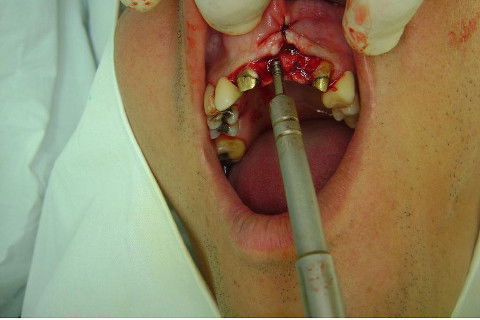

Cirurgia realizada hoje de manhã...No planejamento percebi medindo espessura do rebordo com especímetro que as medidas não estavam muito boas, ou o ideal, em torno de 4,5 a 5 mm ate´o terço médio do rebordo e melhorava no final, com 6 a 7 mm. Optei então por uma pequena expansão usando os expansores rosqueáveis. Aconteceu uma pequena fenestração na hora da fixação dos implantes, especialmente na região do 22 que fraturou o início da tábua óssea, mas não me preocupei porque não foi mais do que 2 mm de fratura em direção apical, o implante ficou infraósseo e com boa estabilidade (60 N no 21 e 40 N no 22). Esta fratura tb não deixou osso completamente solto, foi do tipo galho verde, deixei em posição e suturei normalmente. Só não fiz e nem estava planejado carga imediata mesmo, mais pelo motivo da oclusão inadequada do caso.